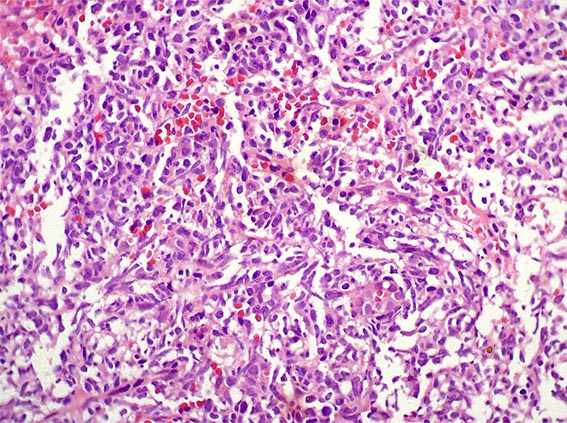

The patient is a 41-year-old woman with constitutional symptoms. Among the many studies undertaken to determine its cause, pyuria and microscopic hematuria were found in the urinary sediment, and, by ultrasonography, a ill-defined mass was evidenced on the renal upper pole of the left kidney.

A biopsy of the mass was obtained. See the images.

Figure 3. H&E, X400.